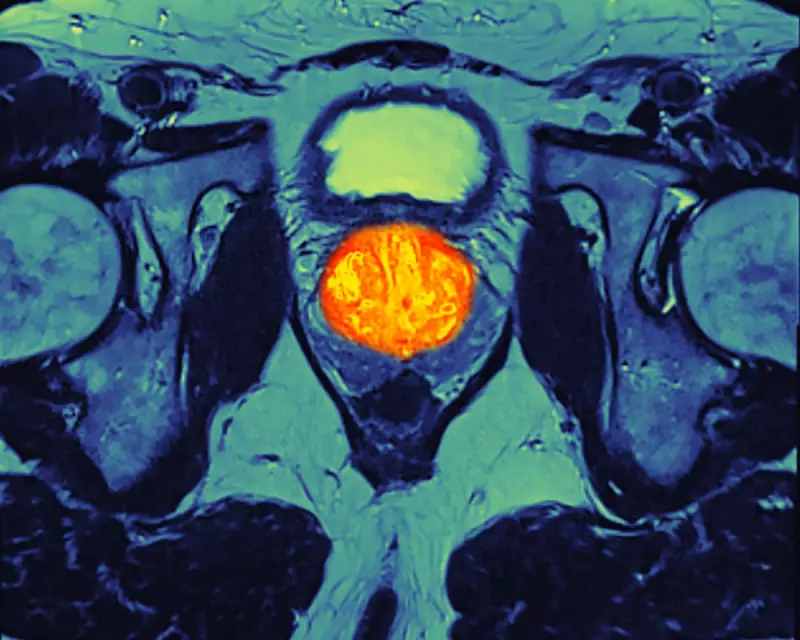

Abiraterone works by starving cancer cells of the hormones they need to grow. It will be administered in combination with the steroid prednisolone.